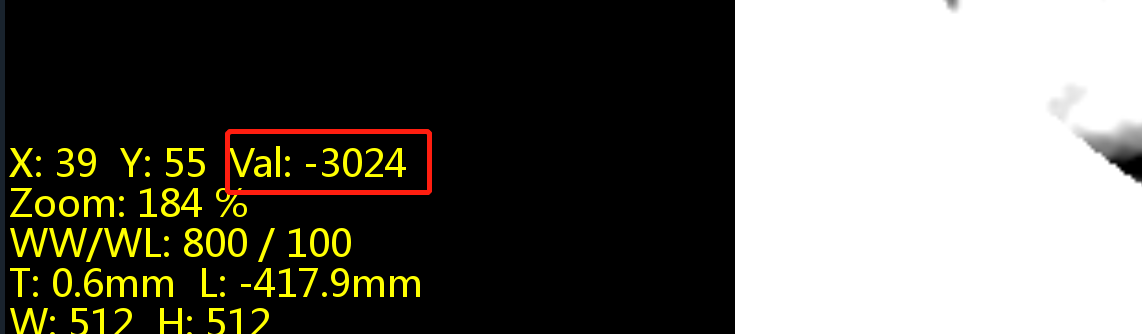

https://blog.csdn.net/liushao1031177/article/details/117696381 如果遇到下面这种有明显边界的ct影像,如何才能区分哪些是有效的CT值,哪些是背景值?

我们可以根据0028,0103内值来区分图像是否被填充过,如果pixel representation为0,则该CT图像未被填充过,其内部像素值都表示有效CT数值;如果pixel representation为1,则该CT图像内有两部分CT值,一部分是有效CT值,另一部分是填充值,只是为了把图像展示成矩形图像;

我遇到的这个数据中,0028,0103为1,则存在0028,0120值,其值为-2000。

由于图像的斜率为1.0,截距为-1024,则-2000就会在线性变换后为-3024;

找一个背景值,可以看到该值为-3024;则像素值为-3024的像素即为填充像素,可以在后处理中过滤掉;